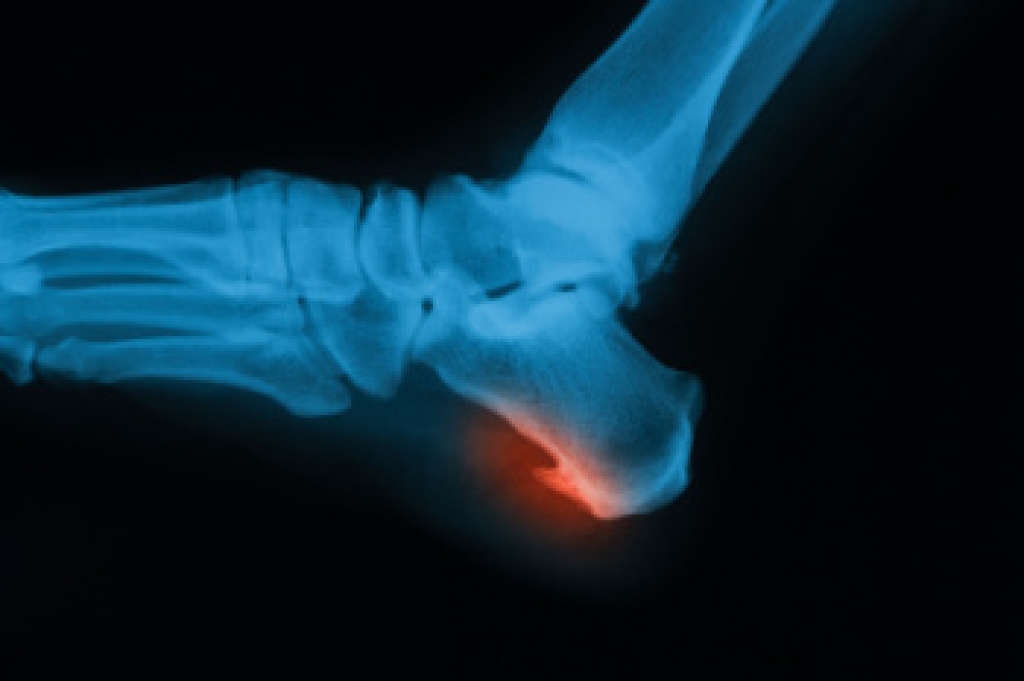

Looking ahead to the summer months, let’s talk flip-flops. Flip-flops tend to be an inexpensive, trendy, colorful, and easy-to-wear option for summer, but because there is little support they may be harmful to your feet. Possible injuries may include damage inflicted to the heel, typically causing severe pain. Additionally, the ligaments in the arch may be affected, which may result from improper support if continued over long periods of time. Spraining the ankle can be connected to lack of arch support, which may occur when rolled to one side. This can be alleviated when proper shoes are chosen for summer wear. There are several choices available for these “fun” shoes, including sandals with a supportive outer heel, cork soles in place of rubber soles, and solid straps that may help to hold the foot in place. Your feet will look good and, more importantly, feel good when the right shoes are chosen.

Yes. Since flip-flops are relatively weak and do not provide the same amount of support as sneakers, people who wear flip-flops regularly are more susceptible to injuries. On top of that, the open nature of the shoe makes your feet more prone to other problems, such as cuts and even infections. Common injuries and ailments include: